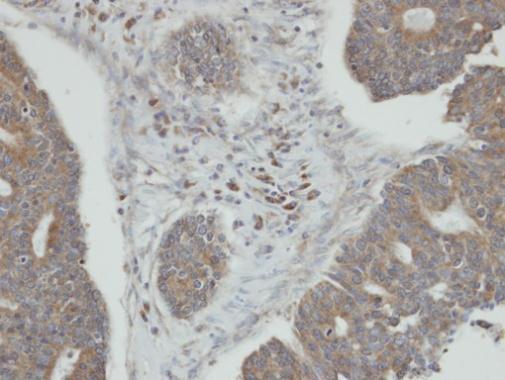

Immunohistochemical analysis of paraffin-embedded human endo mitral ovarian cancer, using PPM1K(GTX105394) antibody at 1:100 dilution.

Antigen Retrieval: Trilogy™ (EDTA based, pH 8.0) buffer, 15min